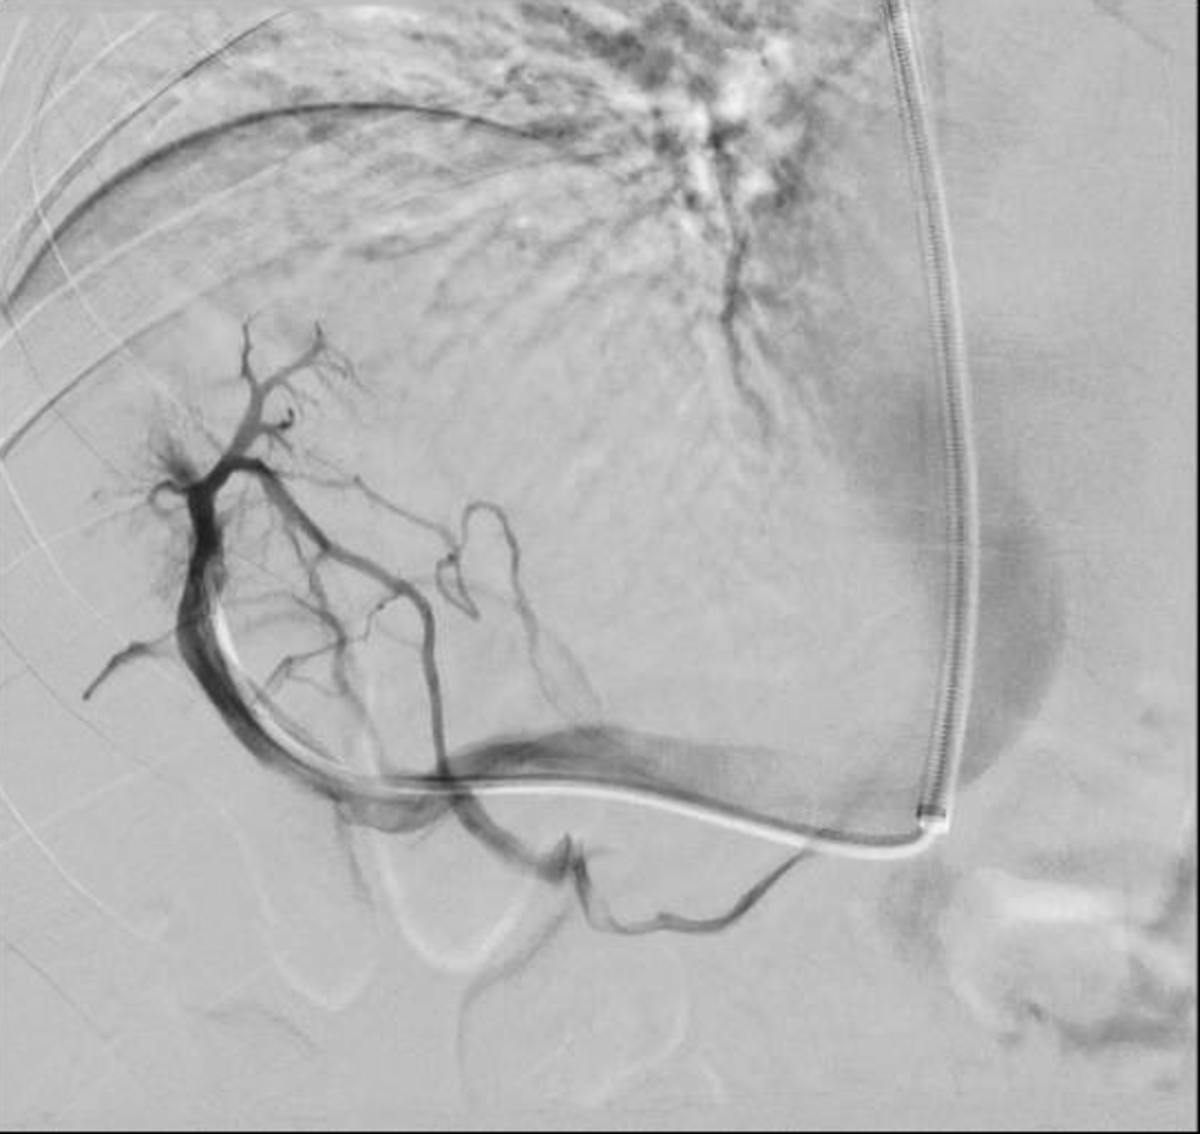

19M, no PMH, w/ abnormal liver function tests. He reports trauma to the abdomen during a fist fight 1 year prior. He has not had jaundice, nausea, or vomiting. Liver tests reveal ALT 78 U/L (normal: 0-35 U/L), AST 72 U/L (normal: 0-35 U/L), total bilirubin 1.4 mg/dL (normal: 0.3-1.2 mg/dL), alkaline phosphatase 240 U/L (normal: 36-92 U/L), and normal albumin. CBC is normal except for a platelet count of 140,000/µL (normal: 150,000-300,000/µL). CT scan reveals hepatomegaly and caudate hypertrophy. A procedure is performed as shown in the figure. What is the best next step in management?

• The patient has Budd-Chiari syndrome with the CT findings supportive of hepatic vein outflow obstruction (caudate lobe hypertrophy as the lobe maintains its direction drainage to the IVC) and venogram showing very diminutive hepatic veins with intrahepatic venous to venous collaterals with a spider web appearance.

• Given that the patient does not have features of decompensated cirrhosis, nor acute liver failure, there is no indication for interventional radiology treatment with angioplasty, TIPS, or for liver transplantation.

• These could be considered if initial therapy with systemic anticoagulation fails, as determined by worsening liver or renal function, or the development of ascites or hepatic encephalopathy. Evaluation for a hypercoagulable state and anticoagulation is the usual first step in this setting.